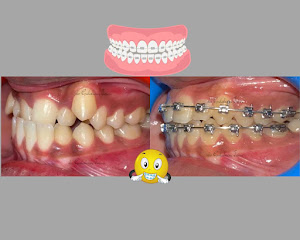

Welcome to our gallery

See how our company transforms ideas into reality. This gallery is a visual testament to our work and achievements.